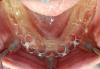

Bier Опубликовано 28 мая, 2012 Поделиться Опубликовано 28 мая, 2012 просто варварское отношение к мягким тканям... Ссылка на комментарий

doctore Опубликовано 28 мая, 2012 Автор Поделиться Опубликовано 28 мая, 2012 Вот чувствуется разница в оценках ортопедов и хирургов .Спасибо! В таких кейсах не важна розовая эстетика-ее все равно никто не оценит. Ссылка на комментарий

kriokov Опубликовано 28 мая, 2012 Поделиться Опубликовано 28 мая, 2012 просто варварское отношение к мягким тканям... кератинизированной десны не много, но видимо гигиена нормальная, если работе 2 года 1 Ссылка на комментарий

Bier Опубликовано 28 мая, 2012 Поделиться Опубликовано 28 мая, 2012 Вот чувствуется разница в оценках ортопедов и хирургов .Спасибо! В таких кейсах не важна розовая эстетика-ее все равно никто не оценит. Владислав, вообще-то кератинизированная десна создается и сохраняется в первую очередь с медицинской точки зрения и уж в последнюю с розово-эстетической )) Ссылка на комментарий

Ст@ся Опубликовано 28 мая, 2012 Поделиться Опубликовано 28 мая, 2012 Вот чувствуется разница в оценках ортопедов и хирургов .Спасибо! В таких кейсах не важна розовая эстетика-ее все равно никто не оценит.Я бы даже как ортопед, судя по фотографиям после операции, подсадила СДТ вестибулярно.Но, судя по фотографиям с отдаленной функцией, все нормально и стабильно Ссылка на комментарий

doctore Опубликовано 28 мая, 2012 Автор Поделиться Опубликовано 28 мая, 2012 Владислав, вообще-то кератинизированная десна создается и сохраняется в первую очередь с медицинской точки зрения и уж в последнюю с розово-эстетической ))Конечно, соглашусь с Вами.Здесь 2 момента- проект был социальный и хирургия пациентом не оплачивалась, и обьем кератинизированной десны, на мой взгляд, не критичен.Но при прочих равных, сегодня это было бы сделано по умолчанию. Ссылка на комментарий